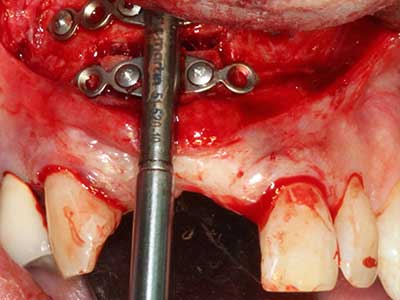

Fig. 27: 21-year-old patient after conversion osteotomy with persistent retrognathy with class II dysgnathy.

Fig. 28: During removal of metal, the basal chin regions are separated with the Piezomed while retaining the lingual blood supply.

Fig. 29: Forward displacement of the chin by 5 mm and fixation with two osteosynthesis plates (KLS Martin). The two mental nerves can be detected in the marginal region.